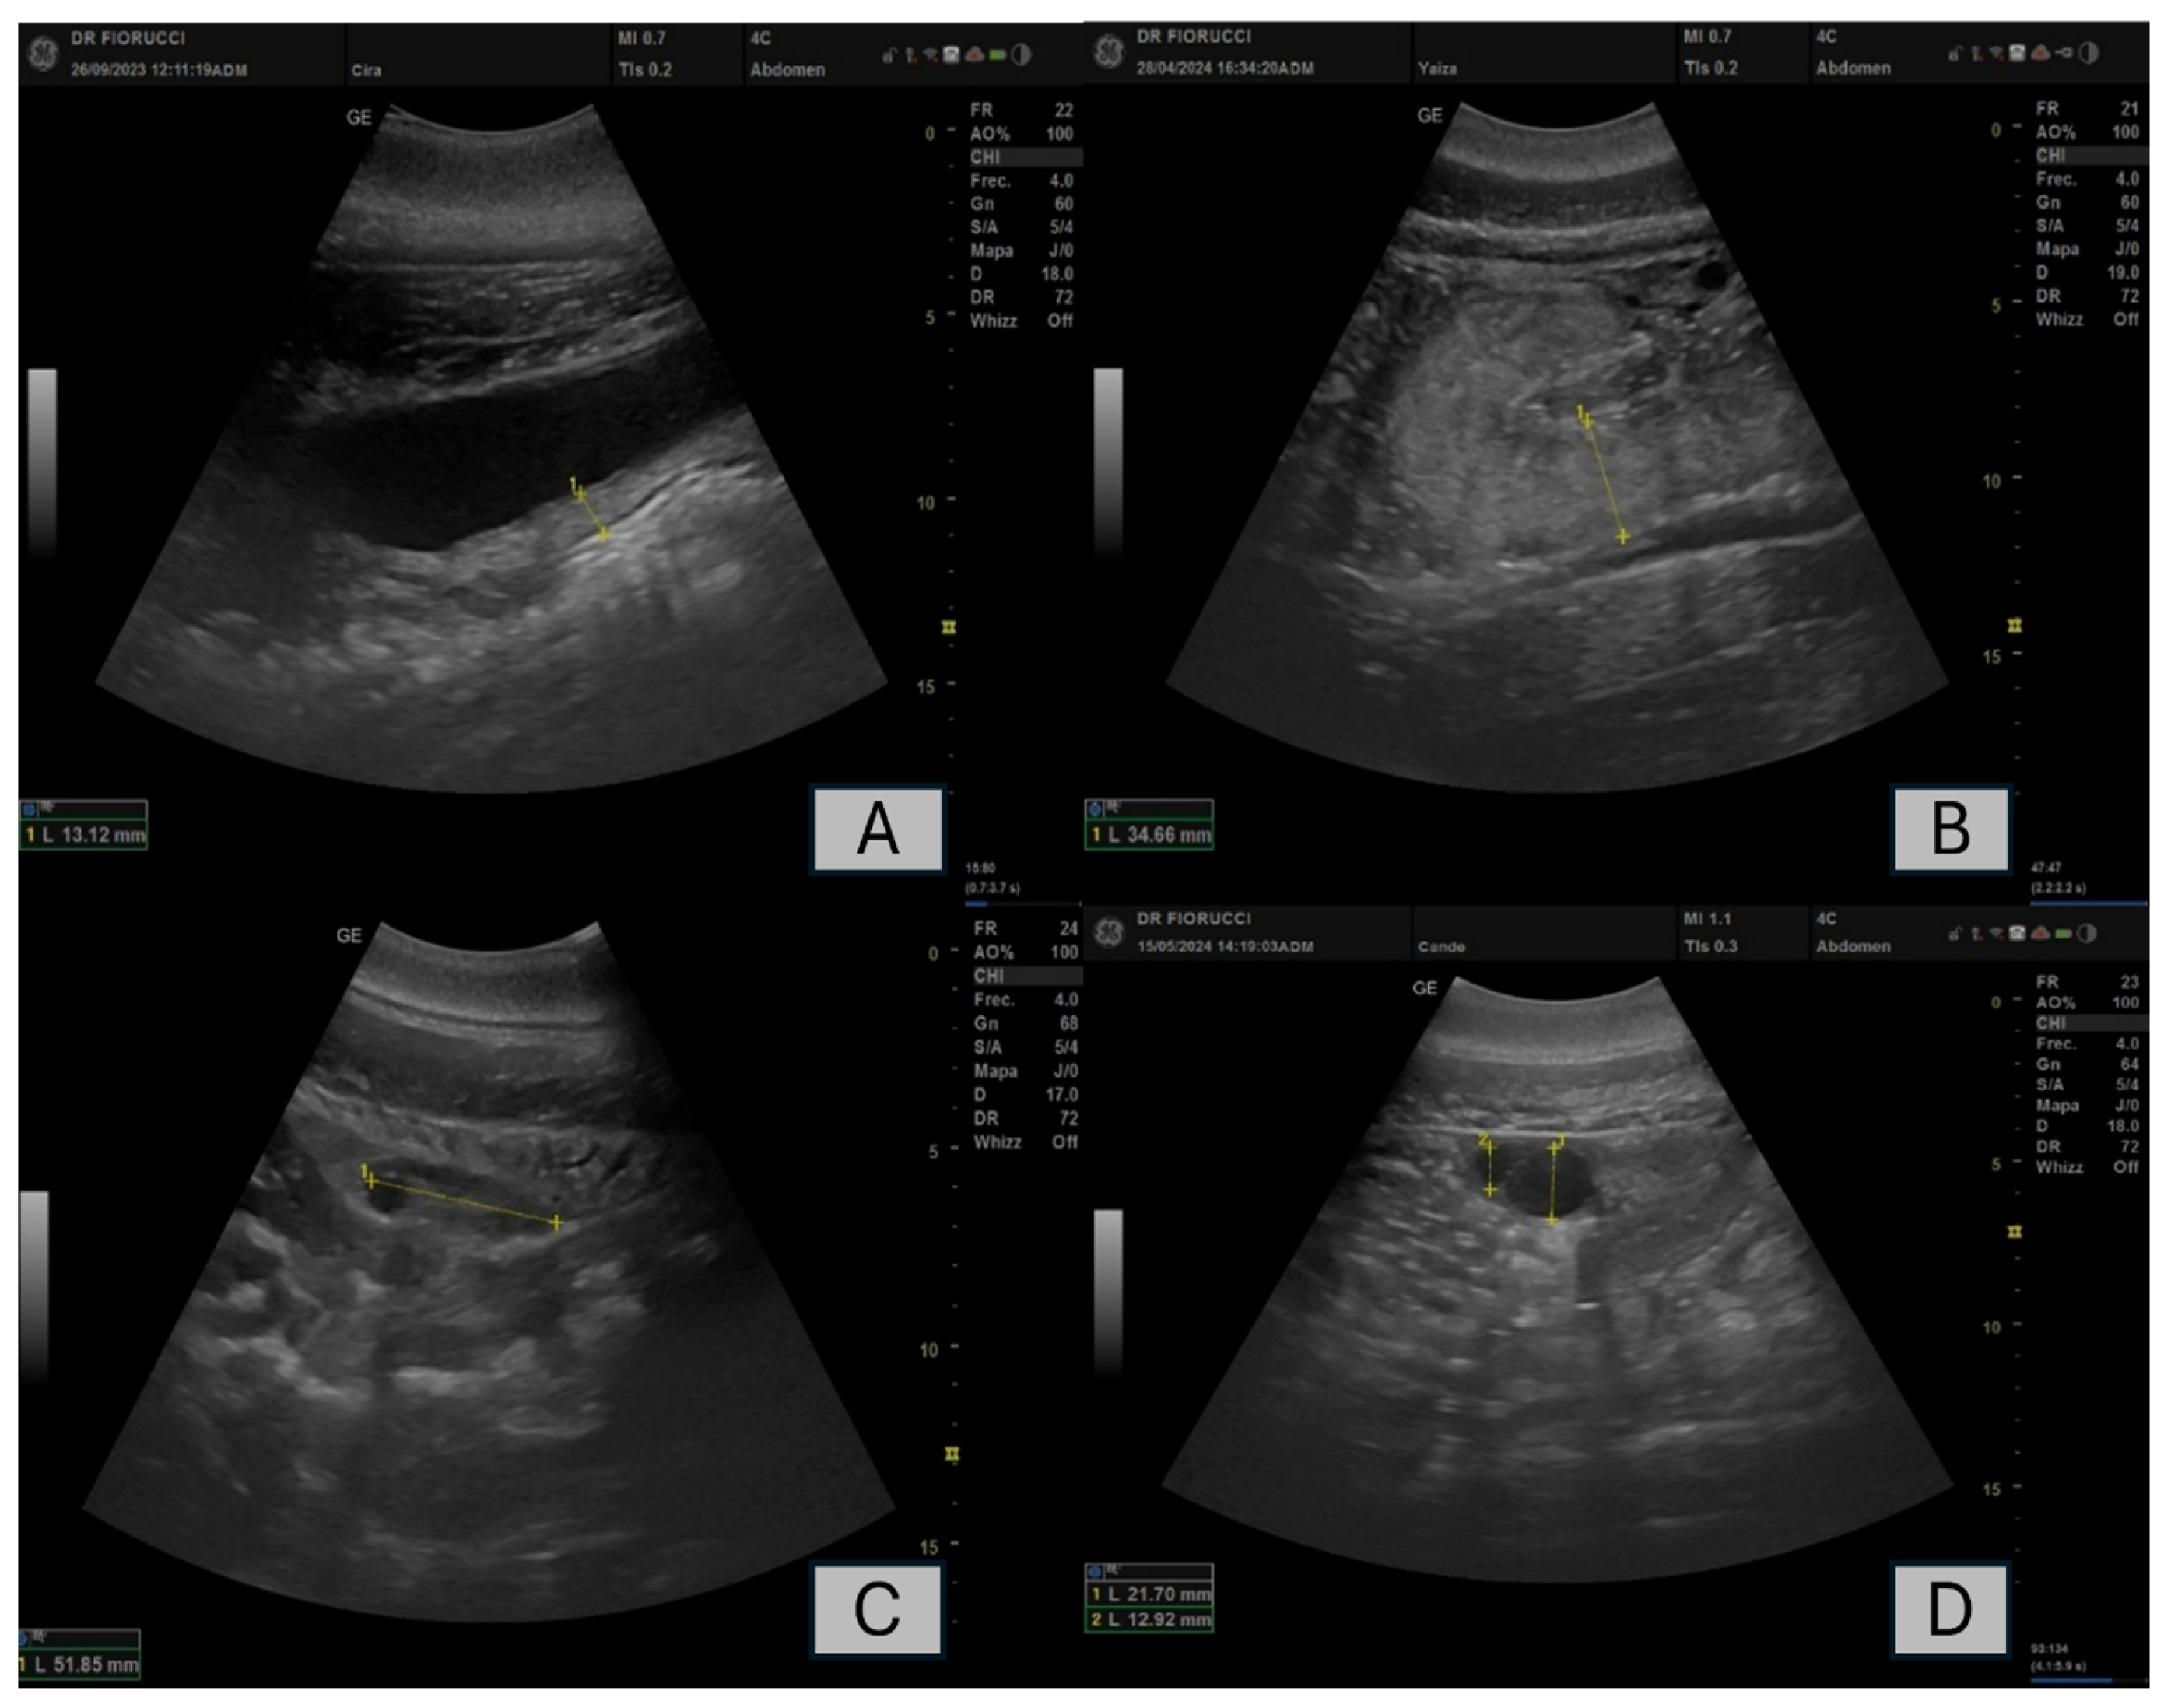

- Any reproductive pathologies detected: Pyometra and follicular cyst. Pyometra has been defined as an infection of the uterus with echographically detectable fluid accumulation, thickening of the walls, and alterations in the blood inflammatory panel. Follicular cysts are defined as follicular structure ≥10 mm in diameter that persists for at least 10 days without evidence of ovulation [13].

| ID_Dolphin | Age (Years) | Pathologies | Duration of Treatment with Altrenogest Prior to Diagnosis of Pathology (Years) |

|---|---|---|---|

| A1 | 42 | Pyometra | 7 |

| A2 | 57 | Follicular Cyst | 2 |

| B1 | 29 | Follicular Cyst | 5 |

| B3 | 52 | Pyometra | 5 |

| B6 | 17 | Follicular Cyst | 9 |

| C3 | 50 | Pyometra | 2 |

| D1 | 16 | Pyometra | 7 |